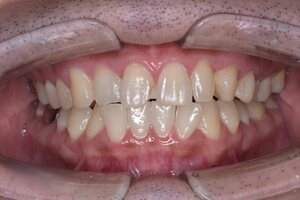

症例③ CR

治療前

治療後

年齢 40代・女性

主訴 前歯の黒いのが気になる

治療内容 右上2番、左上2番

治療費 約2.200円(保険診療3割負担)

(2022年6月現在)

治療期間 1日

リスク・副作用 麻酔がきれた後に痛みがでる可能性がある。

治療方針 両側共に頬側遠心から隣接にかけて、虫歯をとって、CRをつめる。

特記事項 虫歯になりやすい方なので、歯間の清掃指導を行った。

担当者所見 虫歯が歯髄近くまで広がっており、しみるのが続く場合は抜髄の可能性がある。